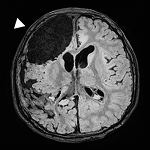

Genetic Architectures and Cell-of-Origin in Glioblastoma.

Front Oncol.2021 Jan 21; 10:615400.

Glioblastoma Cellular Origin and the Firework Pattern of Cancer Genesis from the Subventricular Zone.

J Korean Neurosurg Soc.2020 Jan;63(1):26-33.

The origin-of-cell harboring cancer-driving mutations in human glioblastoma.

BMB Rep.2018 Oct; 51(10):481-483.

Human glioblastoma arises from subventricular zone cells with low-level driver mutations.

Nature.2018 August 01; 560(7717):243-247.